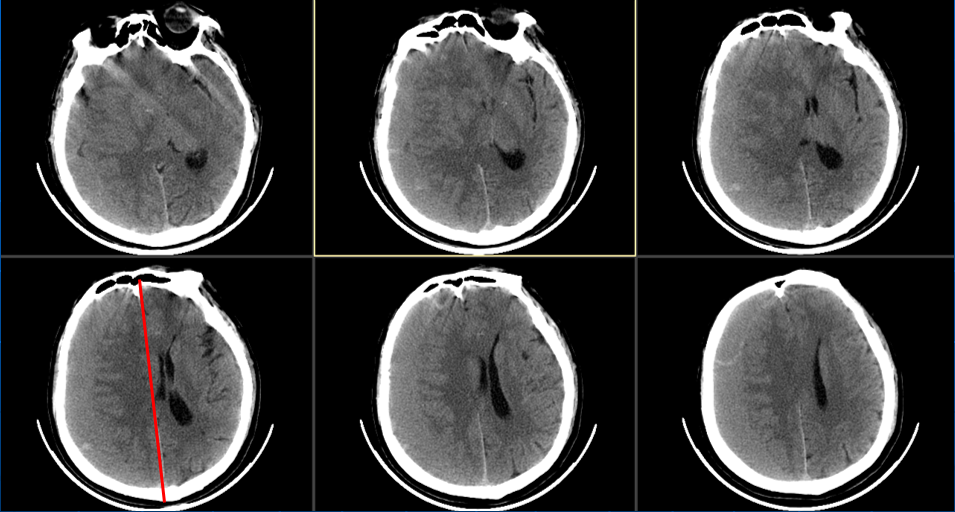

患者约2个月前无明显诱因(否认外伤史)间断出现头痛,头痛为胀痛,左侧较明显,恶心未吐,食欲、睡眠尚可,未予特殊诊治,1个月前患者头痛逐渐加重,思睡,反应略迟钝,行头部CT检查示“慢性硬膜下血肿(双侧)”,于2018年12月15日行颅骨钻孔引流术(左)。术后9天患者恢复良好出院。出院后2周于2019年1月9日患者头痛再次加重,伴有反应迟钝,走路困难,疲乏无力再次就诊,头部CT示“慢性硬膜下血肿(右侧)”,当日再次行颅骨钻孔引流术(右)。术后患者一般状态逐渐好转,无抽搐,无尿便失禁。

2018年12月14日第一次入院

2018年12月16日术后第一日

2018年12月24日出院当日

2019年1月9日第二次入院

术后情况

术后当日(2019年1月16日)

术后3天(2019年1月18日)